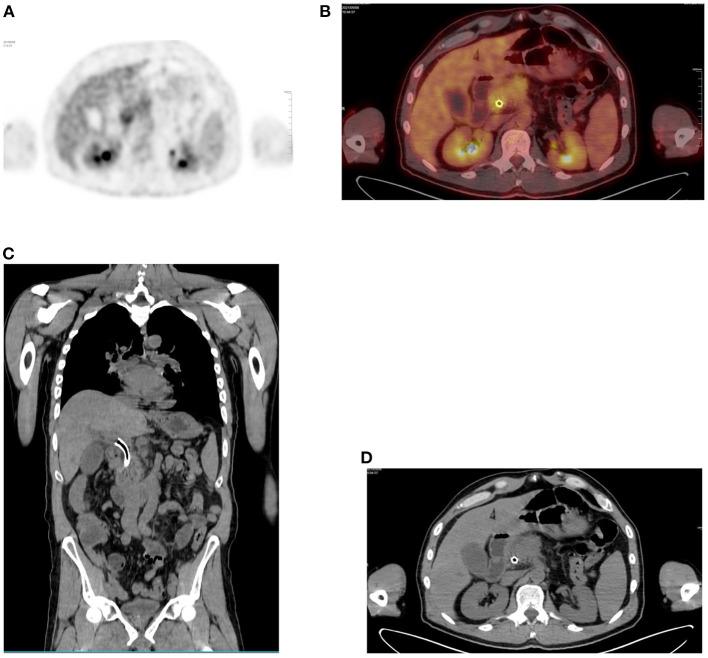

Since its introduction into clinical practice, multimodality imaging has revolutionized diagnostic imaging for both oncologic and non-oncologic pathologies. F-fluorodeoxyglucose (F-FDG) PET/CT imaging which takes advantage of increased anaerobic glycolysis that occurs in tumor cells (Warburg effect) has gained significant clinical relevance in the management of most, if not all oncologic conditions. Because FDG is taken by both normal and abnormal tissues, PET/CT imaging may demonstrate several normal variants and imaging pitfalls. These may ultimately impact disease detection and diagnostic accuracy. Imaging specialists (nuclear medicine physicians and radiologists) must demonstrate a thorough understanding of normal and physiologic variants in the distribution of F-FDG; including potential imaging pitfalls and technical artifacts to minimize misinterpretation of images. The normal physiologic course of F-FDG results in a variable degree of uptake in the stomach, liver, spleen, small and large bowel. Urinary excretion results in renal, ureteric, and urinary bladder uptake. Technical artifacts can occur due to motion, truncation as well as the effects of contrast agents and metallic hardware. Using pictorial illustrations, this paper aims to describe the variants of physiologic F-FDG uptake that may mimic pathology as well as potential benign conditions that may result in misinterpretation of PET/CT images in common oncologic conditions of the abdomen and pelvis.

自从多模态成像技术引入临床实践以来,它已经彻底改变了肿瘤和非肿瘤疾病的诊断成像。利用肿瘤细胞中发生的无氧糖酵解增加(瓦伯格效应)的F-氟脱氧葡萄糖(F-FDG)PET/CT成像,在大多数(即使不是全部)肿瘤疾病的管理中已具有重要的临床意义。由于正常组织和异常组织都会摄取FDG,PET/CT成像可能会显示出几种正常变异和成像陷阱。这些最终可能会影响疾病检测和诊断准确性。成像专家(核医学医师和放射科医生)必须充分了解F-FDG分布中的正常和生理变异;包括潜在的成像陷阱和技术伪影,以尽量减少对图像的错误解读。F-FDG的正常生理过程会导致胃、肝脏、脾脏、小肠和大肠出现不同程度的摄取。尿液排泄会导致肾脏、输尿管和膀胱摄取。由于运动、截断以及造影剂和金属硬件的影响,可能会出现技术伪影。本文旨在通过图片说明,描述可能模仿病变的生理性F-FDG摄取变异,以及在腹部和骨盆常见肿瘤疾病中可能导致PET/CT图像误判的潜在良性情况。